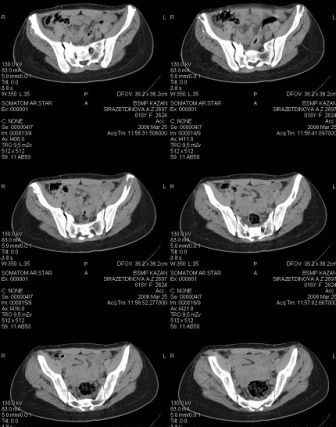

Re: Неправильно сросшийся перелом костей таза

Предоставляю срезы. Если пациентку функционально ничего не беспокоит, стоит ли навязывать ей лечение.